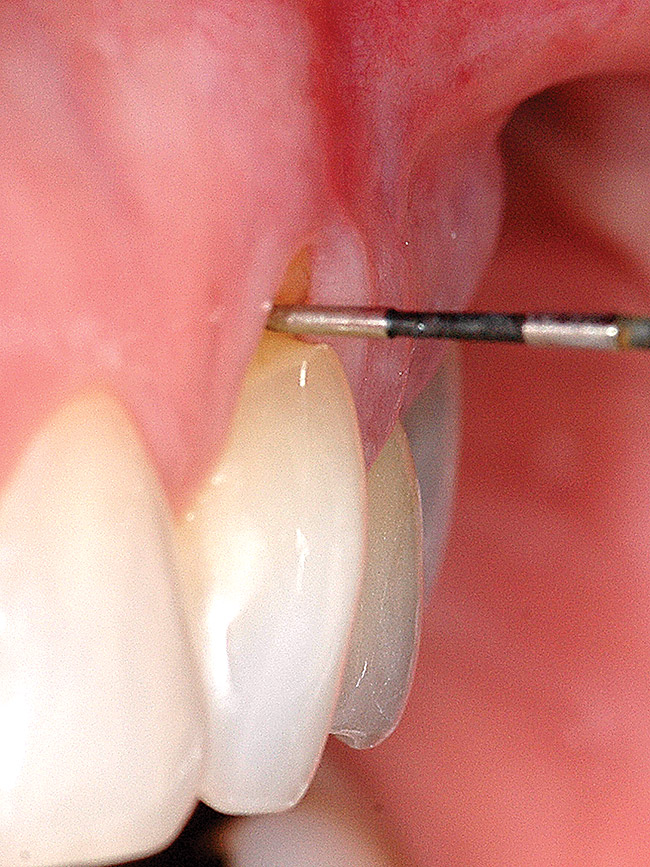

Fig 3 and Fig 4. After mobilization of the marginal tissue, the sharp margins of the lesion were flattened and the enamel overhang was beveled.